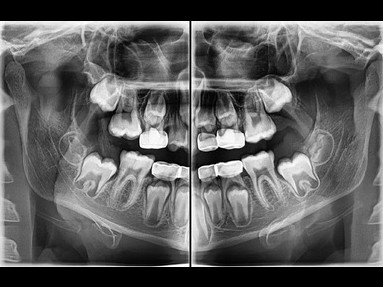

FUNCIÓN INSIGHT DE SEGUNDA GENERACIÓN

Insight PAN es capaz de tomar una multicapa de la imagen panorámica proporcionando un aspecto de profundidad a través de un punto focal único. Insight 2.0 tiene la función de FOV gratuita mejorada para capturar sólo el área de interés.